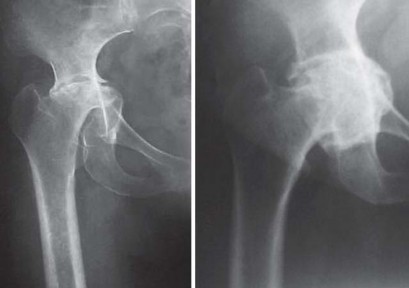

يميل مرضى التهاب المفاصل الروماتويدي اليفعي إلى امتلاك قناة نخاعية فخذية ضيقة جدًا مع عدم توافق بين قطر القناة القريبة والبعيدة. يمكن أن يختلف التجويف الحقي من النوع المشوه (كما يظهر في الشكل 29.1) إلى النوع المنغمس (كما يظهر في الشكل 29.2) أو قد يكون مفصل ورك ملتحم (كما يظهر في الشكل 29.3).

نمط انغماس الورك